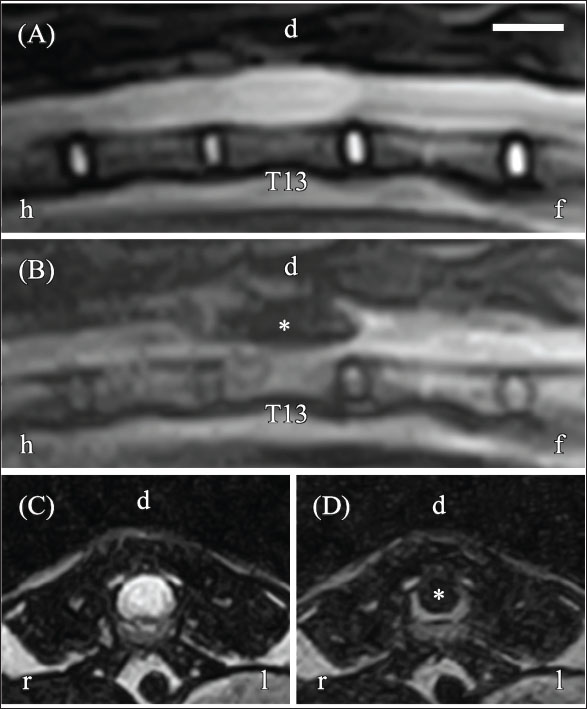

Thoracic and abdominal radiographs revealed no abnormalities. MRI was performed using an AIRIS Vento 0.3-T scanner with a knee coil (Fujifilm, Tokyo, Japan) under general anesthesia. Sequences acquired included the following: T2-weighted sagittal and transverse sequences [repetition time (TR), 3000 ms; echo time (TE), 120 ms; slice thickness, 2.5 mm; gap, 0 mm; field of view (FOV), 300 mm; matrix, 256 × 256; number of excitations (NEX), 8]; T1-weighted sagittal and transverse sequences (TR, 300 ms; TE, 15 ms; slice thickness, 2.5 mm; gap, 0 mm; FOV, 300 mm; matrix, 256 × 256; NEX, 5); pre- and post-gadolinium (Omniscan; GE Healthcare) (dose, 0.1 mmol/kg; delay after injection, approximately 1 minute); and fluid-attenuated inversion recovery (FLAIR) sagittal and transverse sequences (TR, 9,000 ms; TE, 100 ms; slice thickness, 2.5 mm; gap, 0 mm; FOV, 300 mm; matrix, 256 × 256; NEX, 2). The total imaging time was 100 min. MRI revealed a lesion on the dorsal aspect of the T13 spinal cord that appeared hyperintense on T2-weighted images (T2WI) (Fig. 2A and C) and hypointense on both T1-weighted and FLAIR images (Fig. 2B and D). The lesion measured 6.0 mm × 5.0 mm × 18.3 mm and showed no enhancement following gadolinium intravenous administration. These findings indicated a fluid-filled lesion; however, it was not possible to determine whether the lesion was intramedullary or intradural–extramedullary.

Fig. 2. Magnetic resonance imaging (MRI) of the thoracolumbar spinal cord on day 1. (A) Sagittal T2-weighted imaging (T2WI) reveals hyperintensity within the spinal cord. (B) Sagittal fluid-attenuated inversion recovery (FLAIR) imaging displays hypointensity at the same site (asterisk). (C) Transverse T2WI at the T13 level reveals hyperintensity involving nearly the entire spinal cord. (D) Transverse FLAIR imaging at the T13 level shows hypointensity in the same region, consistent with a fluid-filled lesion. However, it was not possible to determine whether the lesion was intramedullary or intradural-extramedullary because its signal characteristics were indistinguishable from the subarachnoid space. Orientation markers: h=head, f=foot, r=right, l=left. Scale bar=1 cm.